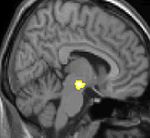

Voxel-based morphometry (VBM) shows brain area structural differences

Positron emission tomography (PET) scans indicate the brain areas which are activated during attack only, compared to pain free periods. These pictures show brain areas that are active during pain in yellow/orange color (called "pain matrix"). The area in the center (in all three views) is specifically activated during CH only. The bottom row voxel-based morphometry (VBM) shows structural brain differences between individuals with and without CH; only a portion of the hypothalamus is different.[33]